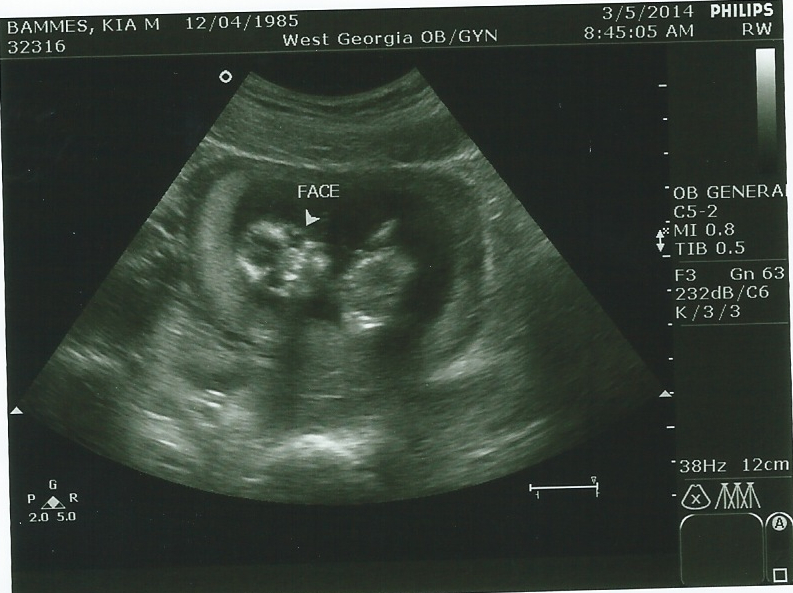

Ultrasound at 14 wks-B or G nub and skull guesses please!